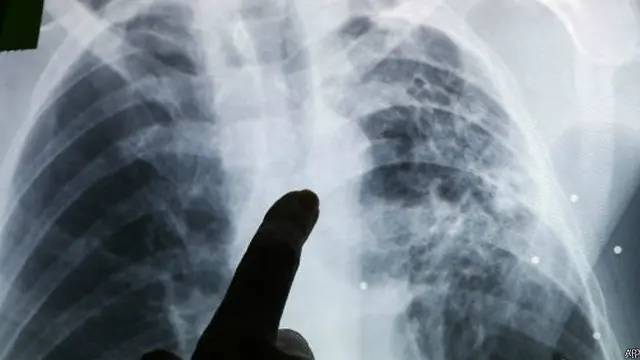

Crédit photo, AP